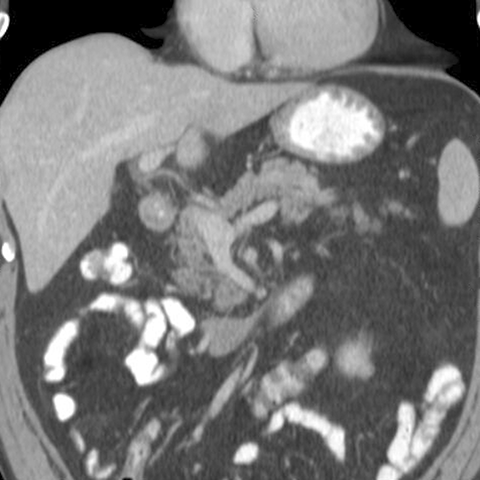

Normal Pancreas, Coronal CT [2 of 3]